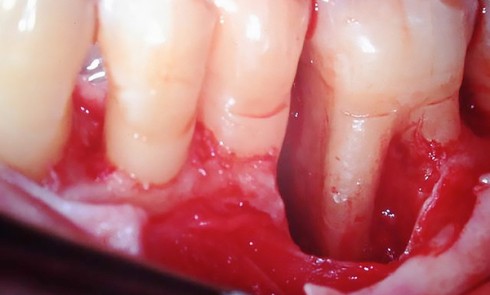

Article réservé à nos abonnés La régénération dans le traitement des défauts infraosseux en 2018

Au fil du temps, différentes techniques chirurgi­cales ont été proposées pour reconstruire les tissus parodontaux en présence de défauts infra­osseux,...